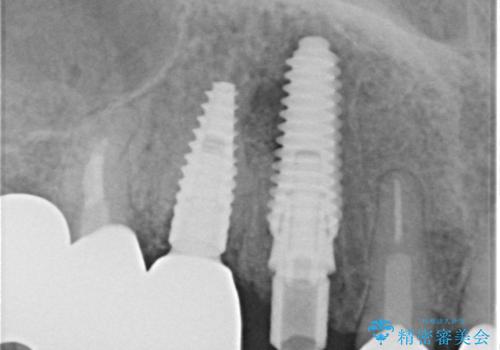

全顎的な治療後に、急遽ニューヨークへ転居されることとなったのですが、治療後から経過観察を行っていた右上犬歯が歯肉縁下に及ぶむし歯のため、クラウンが土台ごと外れてしまったとの連絡がありました。

他の部位にインプラント治療を行っていたことから、こちらの歯に対してもインプラントによる補綴治療を希望されたため、1泊での帰国時に抜歯、インプラント埋入、仮歯の装着を行い、数ヶ月後の帰国時にオールセラミッククラウンの型取りと装着を行う計画としました。